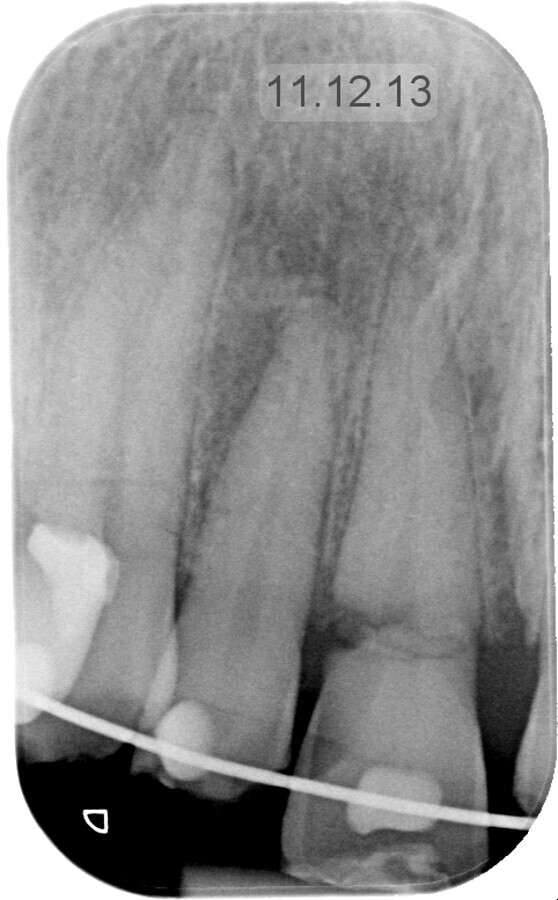

3D- foto van de schedel van meneer Bruinsma vlak na het ongeval

Na plaatsing van een spalk wordt hij naar huis gestuurd en bij de eerstvolgende afspraak komt hij bij dokter Van Minnen terecht. Vanaf dat moment hebben ze vrijwel elke maand een afspraak. Van Minnen vertelt dat de elementen 21 tot en met 13 waren aangedaan. Bij de 21 gaat het om een glazuurafwijking, de 11 en 13 zijn ernstig beschadigd en de 12 ligt er volledig uit. Deze laatste is direct na het ongeluk teruggezet en gespalkt. De wortels van de 11 en 13 zitten er dan nog wel in, maar de prognose van deze afgebroken elementen is vrij slecht. Van Minnen: “Deze wortels hebben we verwijderd en een maand na het letsel hebben we de tandkassen opgevuld met bot om de processus alveolaris zo goed mogelijk te behouden. In maart plaatsten we vervolgens de implantaten en die zijn inmiddels goed vastgegroeid. Als laatste stap van de behandeling komen eind augustus de kronen hierop.”